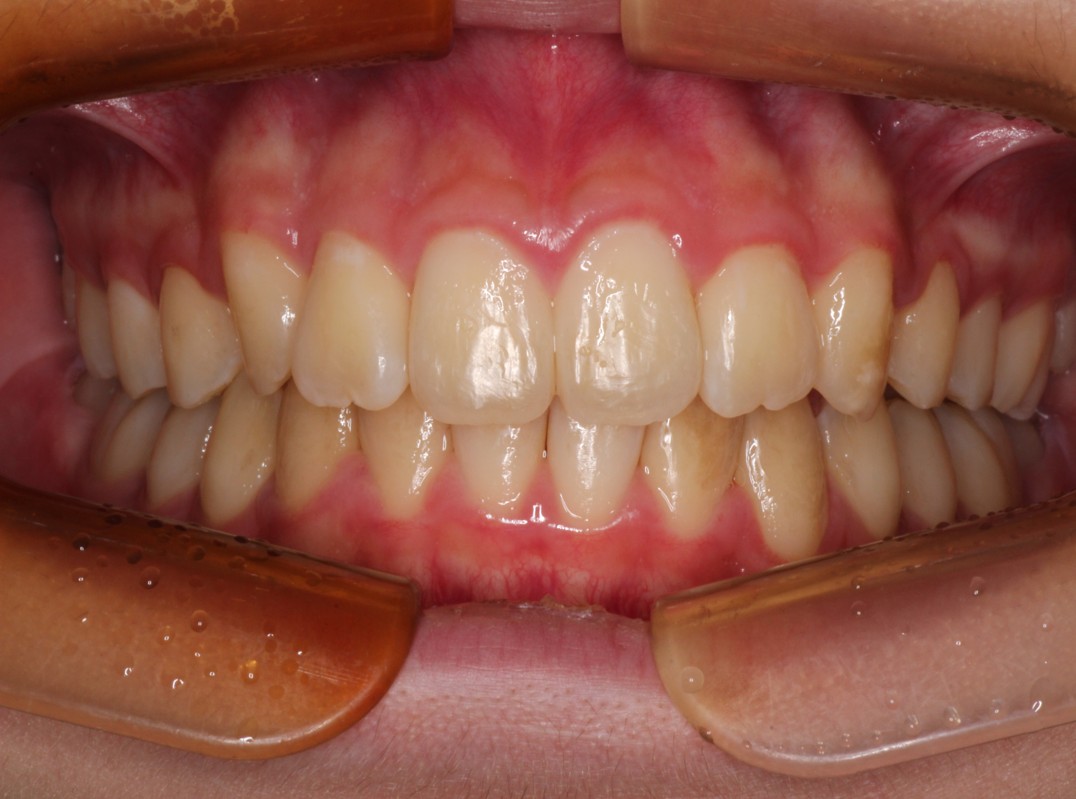

治療後

Ⅰ期治療は前歯の歯並びだけを揃えましたが、奥歯の歯並びも綺麗にしたいとのことだったのでⅡ期治療も行いました。 |